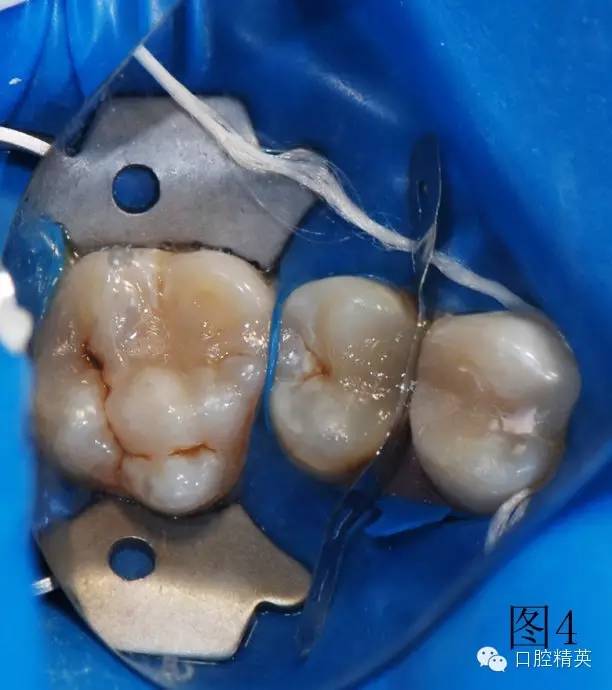

圖2、3為左上第一前磨牙充填結束,上橡皮障,充填另外兩顆牙。使用橡皮障,可以嚴密隔濕,防止樹脂受到污染,增加樹脂與牙齒之間的粘結力,延長充填物的使用壽命。

3顆牙充填完畢,卸下橡皮障夾和障布。